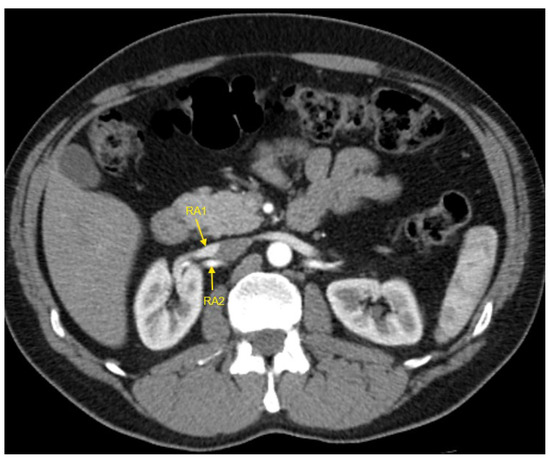

Figure 1, Figure 2, Figure 3, Figure 4 and Figure 5 show examples of some renal vascular abnormalities we identified in our study population.

Figure 4. Contrast-enhanced CT imaging of a 43-year-old male patient with true resistant hypertension showed the presence of two renal arteries in the right kidney, indicated by the yellow arrows. CT—computed tomography; RA1—first renal artery; RA2—second renal artery.